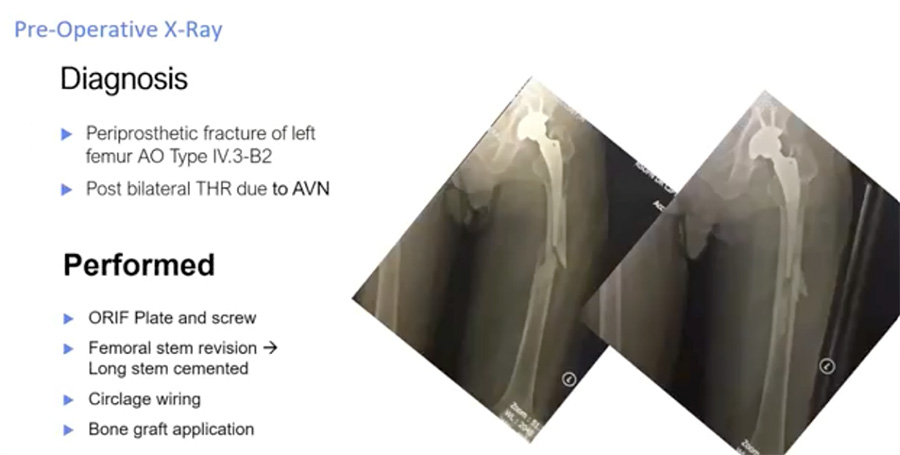

Below are two radiographs of an AO type IV.3–B2 periprosthetic hip fracture in a 56-year-old male. This patient received a total hip replacement seven years previously due to avascular necrosis (AVN). The fracture occurred one month before his hospital admission.

Evidence favors ORIF plus revision of the total hip arthroplasty (rTHA)

Specifically, B2 periprosthetic fractures are indications for long-stem hip arthroplasty revision.1

After ORIF using minimally invasive plate osteosynthesis (MIPO) techniques, the patient’s post-operative x-rays (below) show a well-reduced fracture with a stable implant, the stem of which extends well past the fracture site. To provide the best possible conditions for fracture healing, the new stem should extend at least two femoral diameters past the fracture or defect.